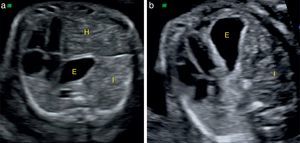

Presencia de herniación hepáticaLa herniación del hígado al tórax la presentan cerca del 50% de los casos de HDC izquierdas, mientras que siempre forma parte del diagnóstico en las HDC derechas. Desde siempre ha sido un factor reconocido como predictor de supervivencia, claramente asociado a peor pronóstico (fig. 1a), y confirmado en varios metaanálisis recientes31,32.

La valoración de la herniación hepática puede realizarse por medio de su visualización directa en el tórax. Existen también signos indirectos, como la posición del estómago, el cual se encuentra desplazado posteriormente en caso de herniación hepática (fig. 3a) o se encuentra muy anterior cerca del esternón en ausencia de esta (fig. 3b). Otro signo indirecto es la desviación del trayecto de la vena umbilical, que nos indica la posición del hígado.